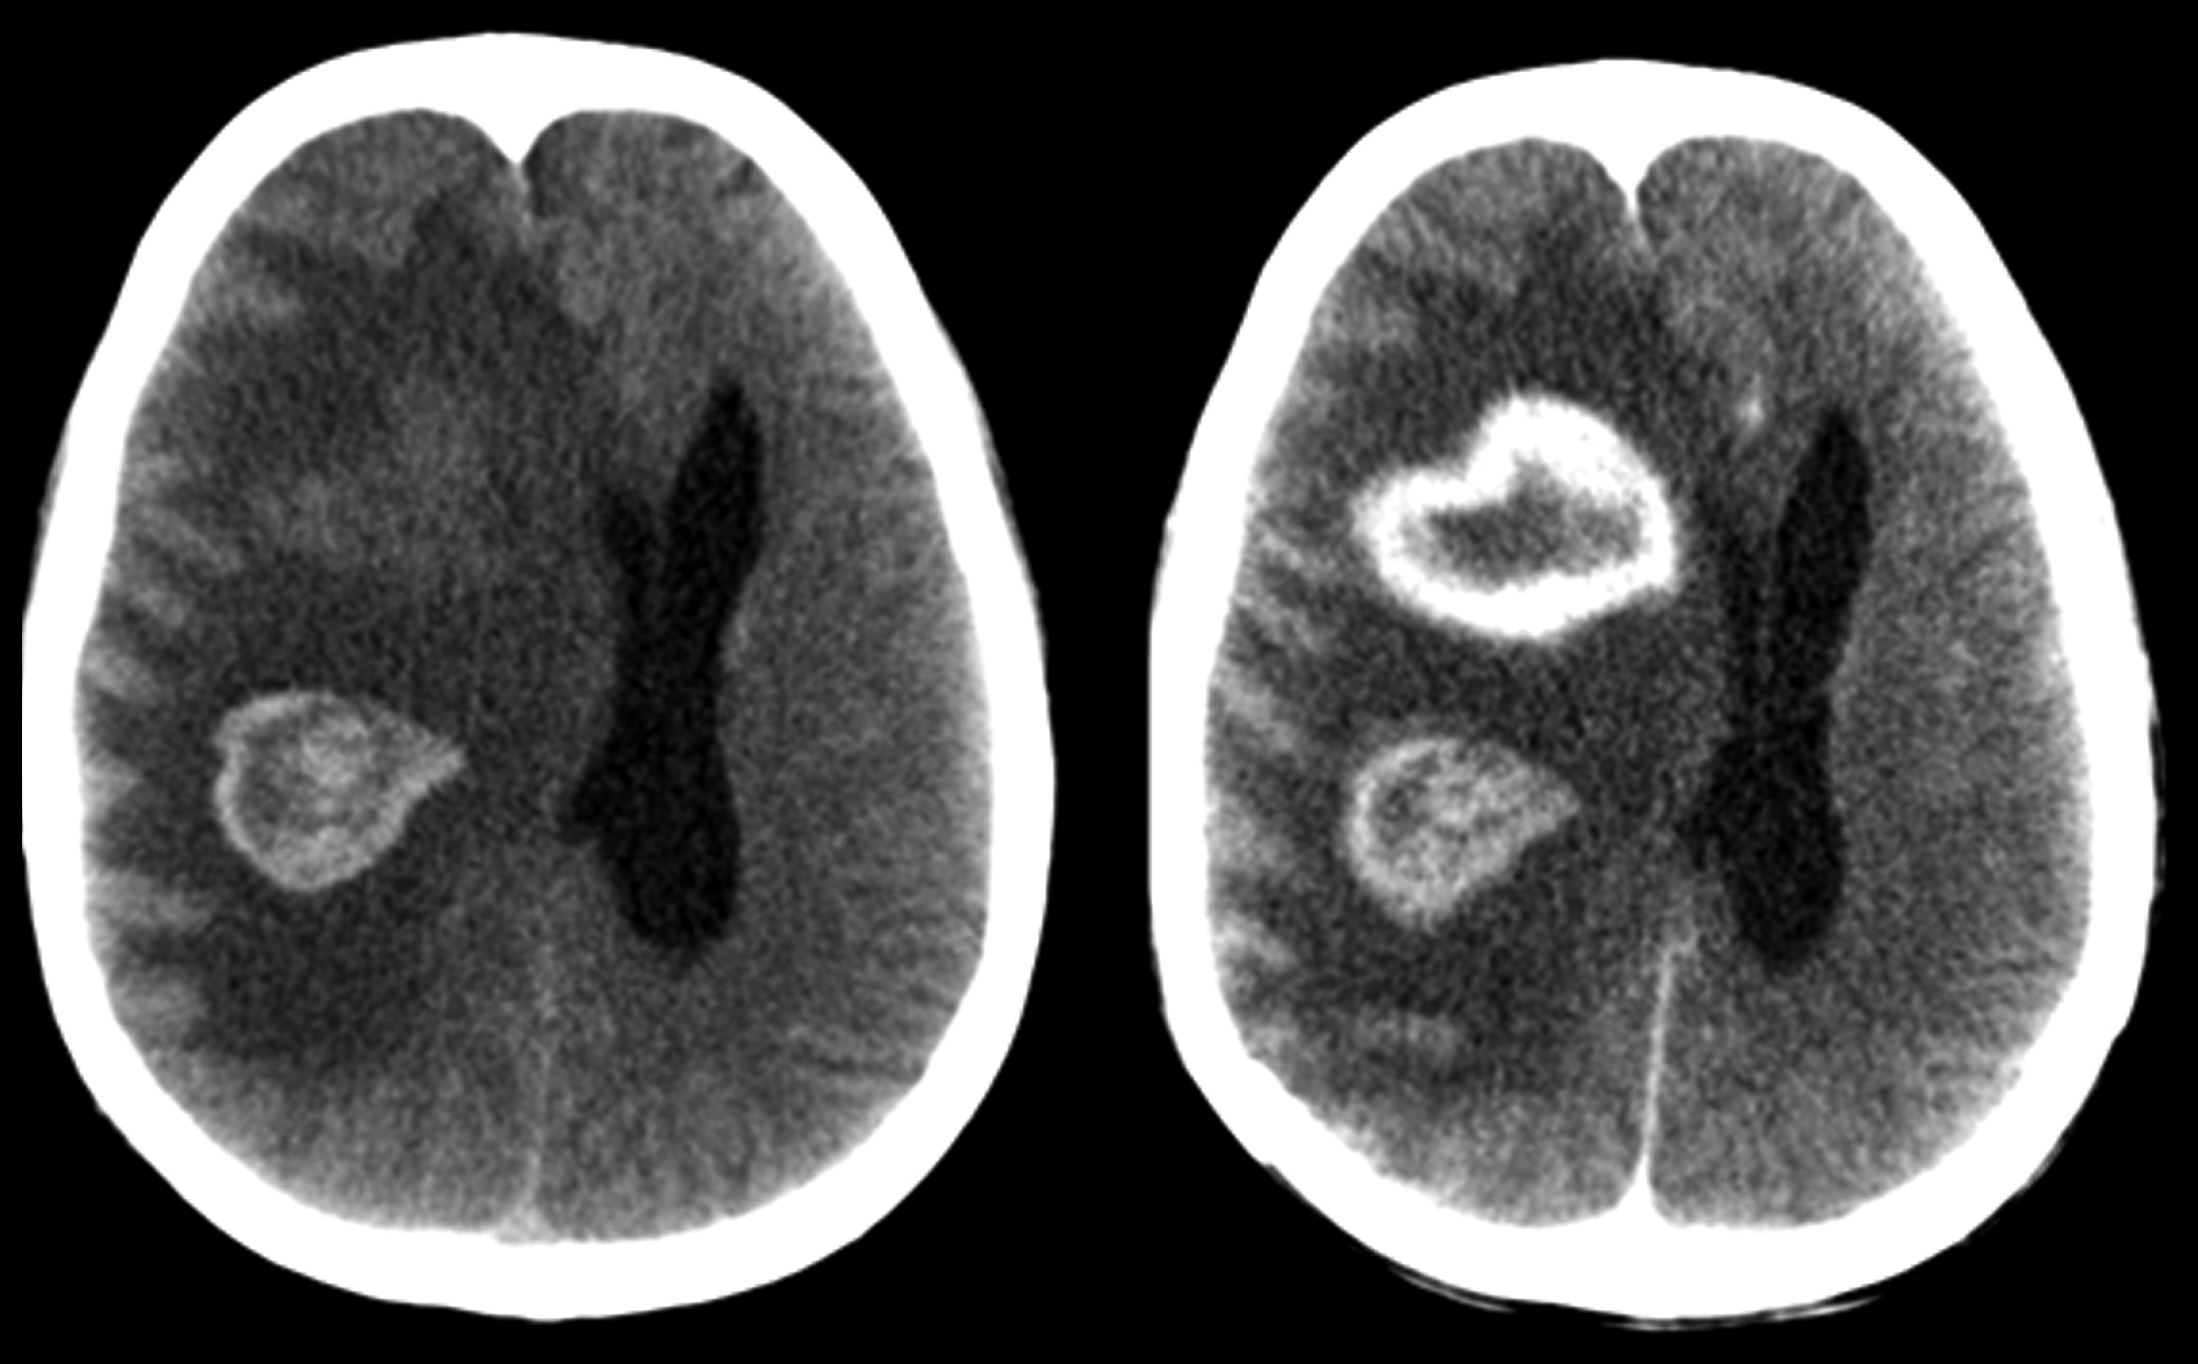

Se realiza TC de cráneo (Fig. 1), donde se constata la presencia de dos lesiones intra-axiales frontales derechas, con sectores espontáneamente hiperdensos en relación a sangrado. Ambas presentan realce en anillo grueso e irregular con el medio de contraste. En RM son de intensidad de señal heterogénea, hipointensas en T2/FLAIR (del inglés “fluid attenuated inversión recovery”), hiperintensas en T1, con realce periférico grueso, continuo e irregular con gadolinio. En secuencias eco de gradientes (GRE) se observan zonas de artificio de susceptibilidad magnética en relación a áreas de sangrado interno. En difusión-ADC (coeficiente de difusión aparente) se objetivan áreas periféricas de restricción y en el estudio de perfusión disminución del volumen sanguíneo cerebral (Fig. 2). Se completó estudio con TC de cuello, tórax, abdomen y pelvis, sin identificarse lesiones sugerentes de compromiso nodal, hepático o esplénico.

Con valores de CD4 de 37 cél/mm3 y carga viral de 283679 copias/ml, presenta peoría clínica, con depresión de conciencia, “score de coma de Glasgow” de 3, requiriendo intubación y asistencia respiratoria mecánica. En TC de control (Fig. 3), se constató aumento del tamaño lesional secundario a sangrado.

Figura 2

a) Corte coronal secuenciada ponderada en T2.

b) Corte axial secuencia GRE.

c) Perfusión, mapa de volumen sanguíneo cerebral.

d) Corte axial ponderada en T1 tras la administración de Gadolinio.

e) Difusión.

f) Mapa de ADC. Las lesiones presentan intensidad de señal heterogénea, hipointensas en T2/FLAIR, hiperintensas en T1, con realce periférico grueso, continuo e irregular con el gadolinio. Asocian restricción en difusión también periférica, concordante con las áreas de realce. En secuencias GRE presentaban sectores de artificio de susceptibilidad magnética, en relación a sangrado. La lesión frontal anterior muestra disminución del volumen sanguíneo cerebral (VSC) en el estudio de perfusión. La lesión posterior presenta importantes áreas de hemorragia que generan artefactos y dificultan la correcta interpretación del estudio de perfusión. Se observa además, importante edema perilesional y efecto de masa locorregional.

Figura 3

Control evolutivo

a) Corte sagital sin contraste.

b) Corte coronal con contraste iv. Frente a la peoría clínica se realizó tomografía de control. Se observa aumento de la lesión, secundario a sangrado intra-tumoral.